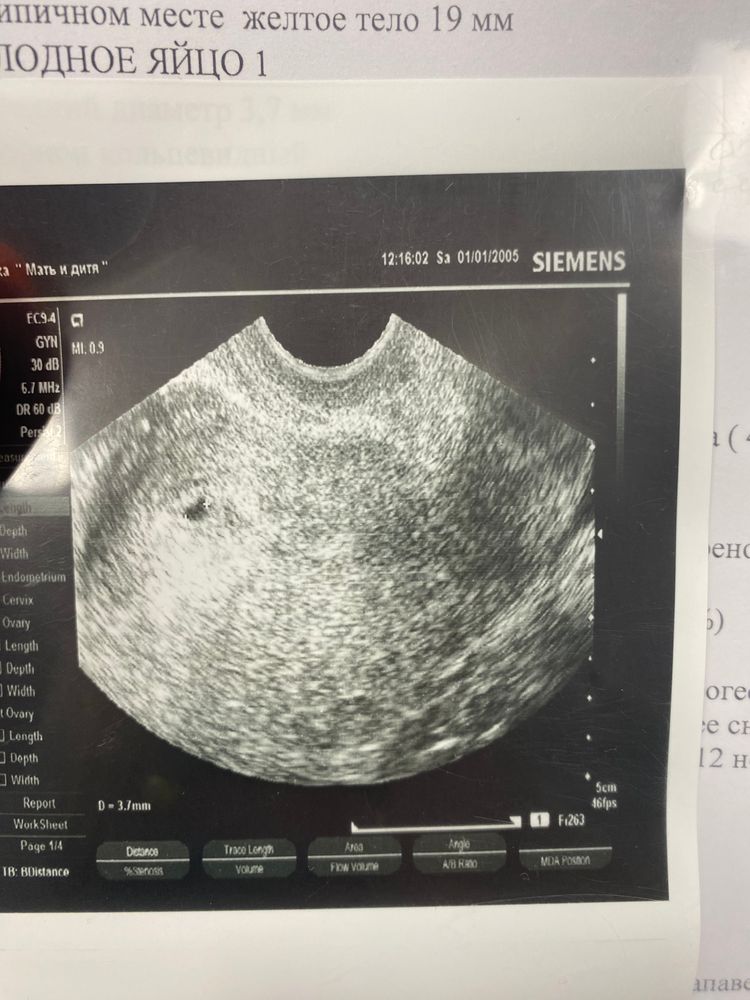

Поздравляю🎉🎊ростите здоровенькими и вам лёгкой беременности.Это так волнительно. Тоже ждала своего малыша 12 лет, позади зб, вб, пролёты. И в четвёртом протоколе эко победа. Поверила в то что это не сон только когда прошла второй скрининг, а до этого страхи накрывали до какой-то паранойи.